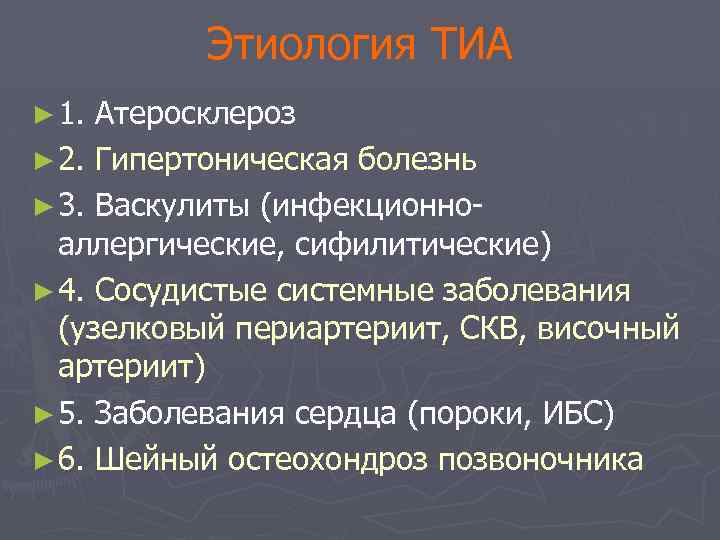

Этиология ТИА ► 1. Атеросклероз ► 2. Гипертоническая болезнь ► 3. Васкулиты (инфекционноаллергические, сифилитические) ► 4. Сосудистые системные заболевания (узелковый периартериит, СКВ, височный артериит) ► 5. Заболевания сердца (пороки, ИБС) ► 6. Шейный остеохондроз позвоночника